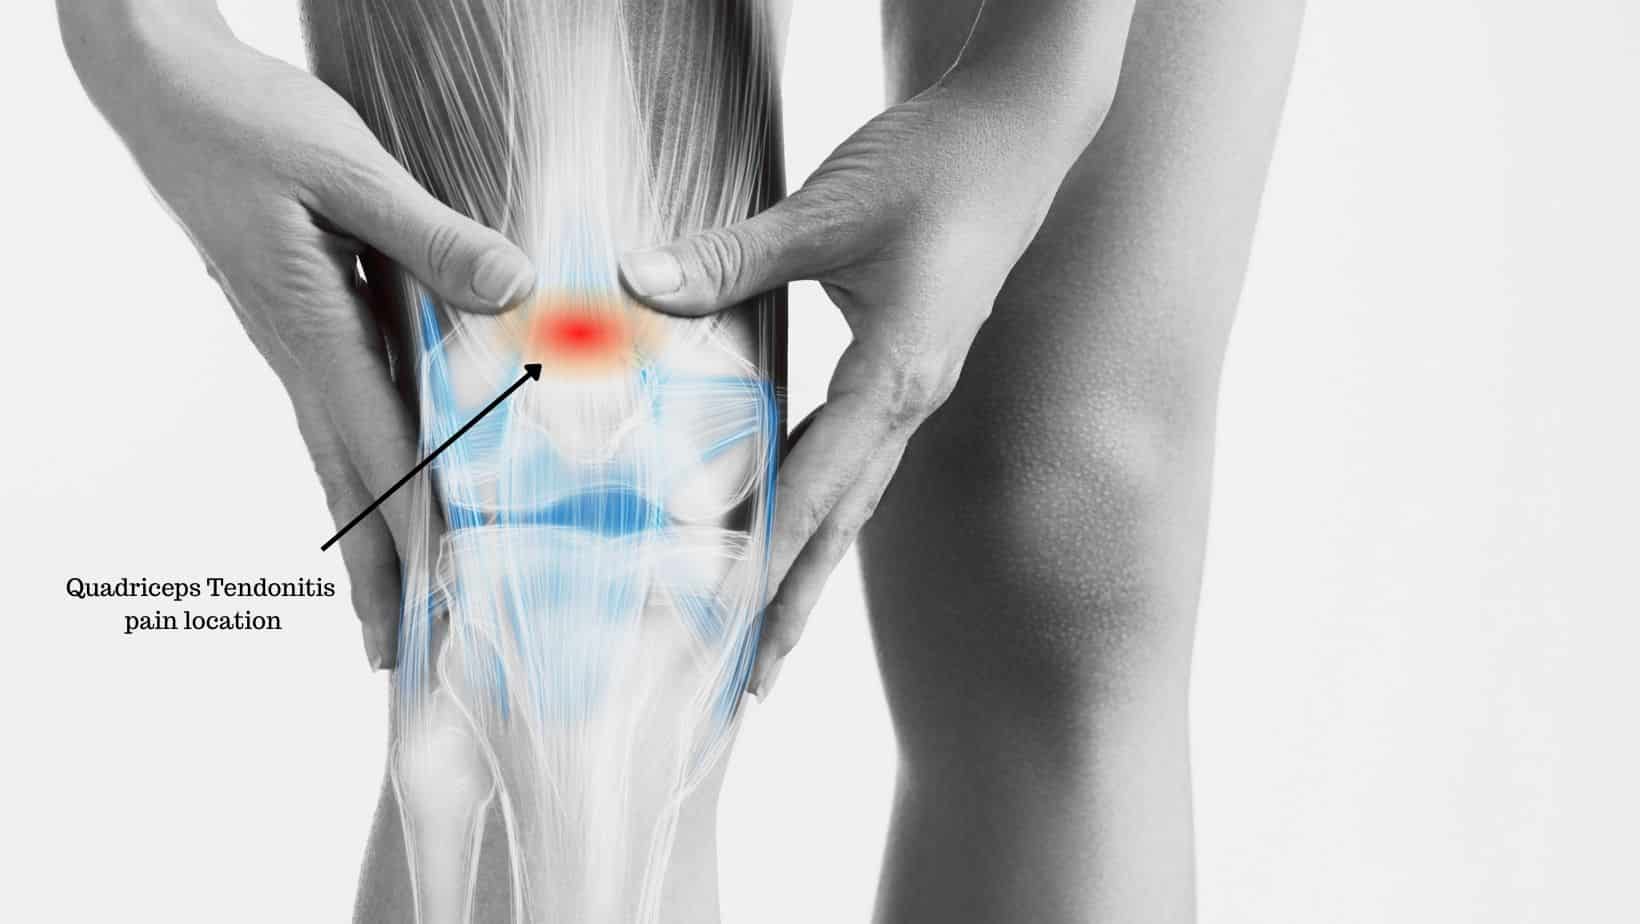

Gân cơ tứ đầu đùi là gì? Khớp gối là một trong những khớp lớn trên cơ thể. Xương bánh chè là xương ‘vừng’ lớn nhất được che phủ phía trước bởi một đường gân nối các cơ lớn ở phía trước đùi (cơ tứ đầu đùi) với xương cẳng chân.Gân cơ tứ đầu đùi rất […]